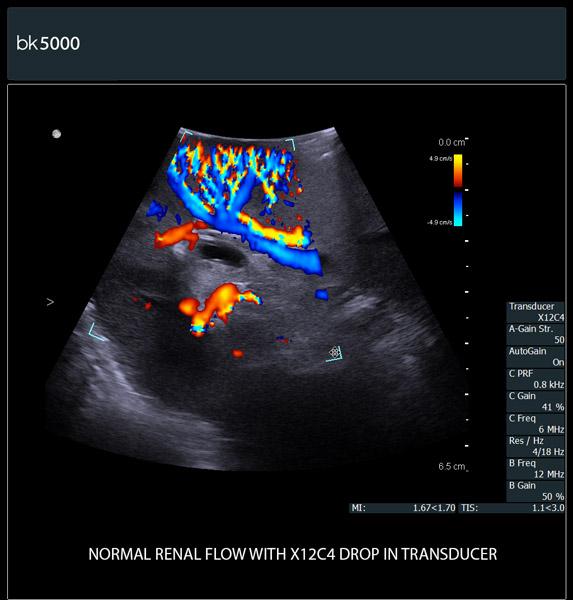

Extremely sensitive color Doppler with superb spatial resolution identifies arterial and venous blood supply to the tumor. This is especially important in procedures where selective clampingis needed. Unsurpassed 3D imaging enables easier identification of key anatomical landmarks and dissection planes.

The unique Drop-In transducer enables access and visualization of complex organs and difficult-to-access anatomy in real-time. For example, in kidney navigation and difficult-to-access endophytic and exophytic tumors, the small, compact, curved linear array Drop-In transducer enables a wider field of view for faster examinations. The specially-designed fin grasped by the robotic arm ensures maximum control and organ contact so you can get the information you need.